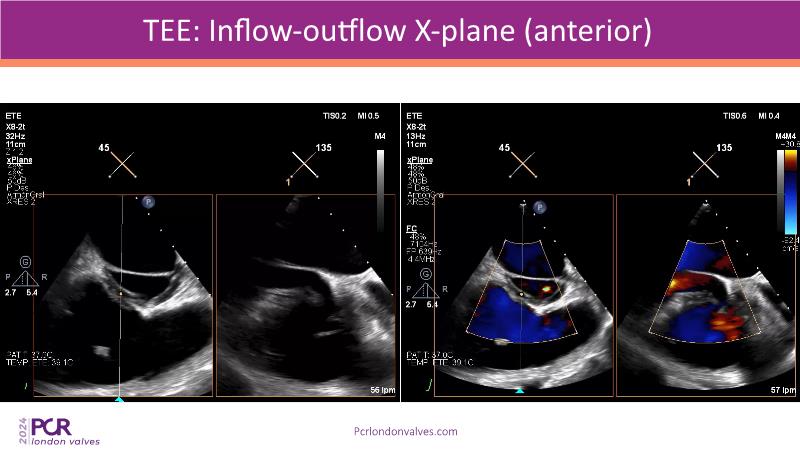

This session examines two compelling cases: a 78-year-old woman with paroxysmal atrial fibrillation, chest trauma, an osteoporotic sternum fracture, and NYHA II exertional dyspnoea, and an 82-year-old man with chronic three-vessel coronary artery disease, bradycardic AF, peripheral arterial disease, spinal stenosis, and chronic kidney disease. Through their study, discover the intricate anatomy of atrioventricular valves, the therapeutic challenges they pose, and the growing significance of transcatheter edge-to-edge repair (TEER) therapies. The discussion also highlights the value of multidisciplinary strategies in managing complex valve diseases effectively.